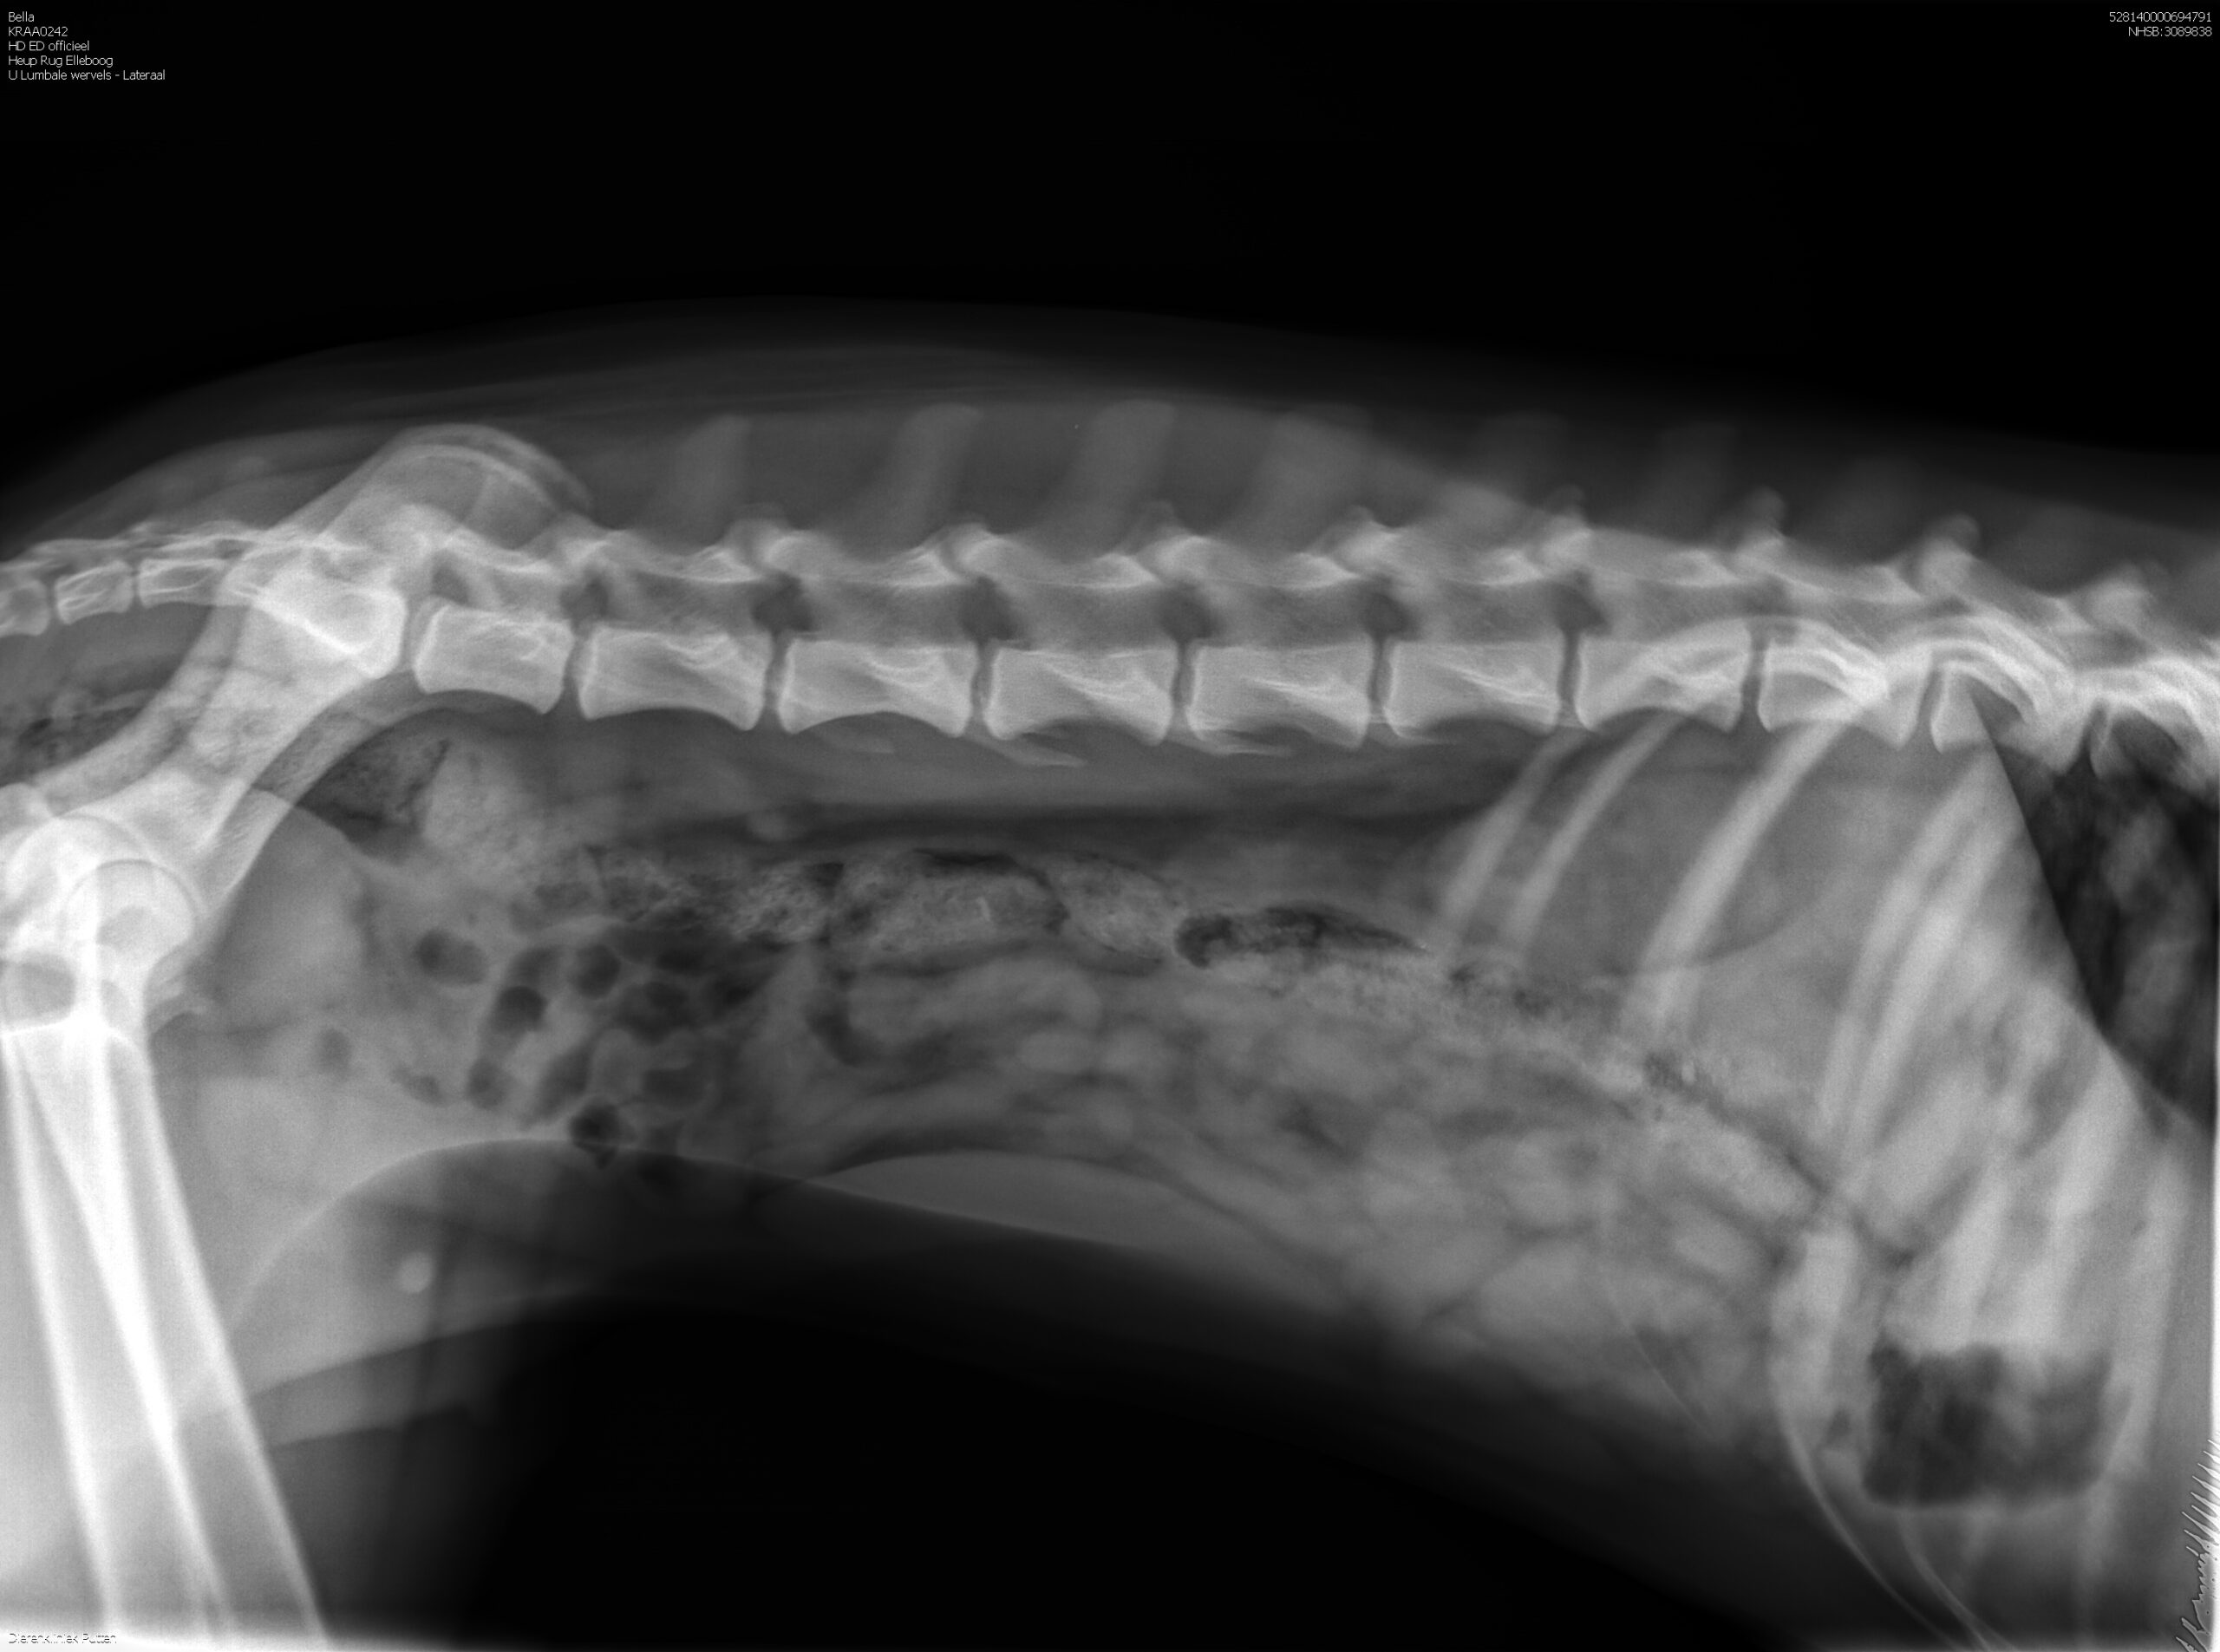

HD-A (Norbergwaarde 37.5, Botafw. 0), ED-0, Rug 100%

Röntgen foto’s Bella